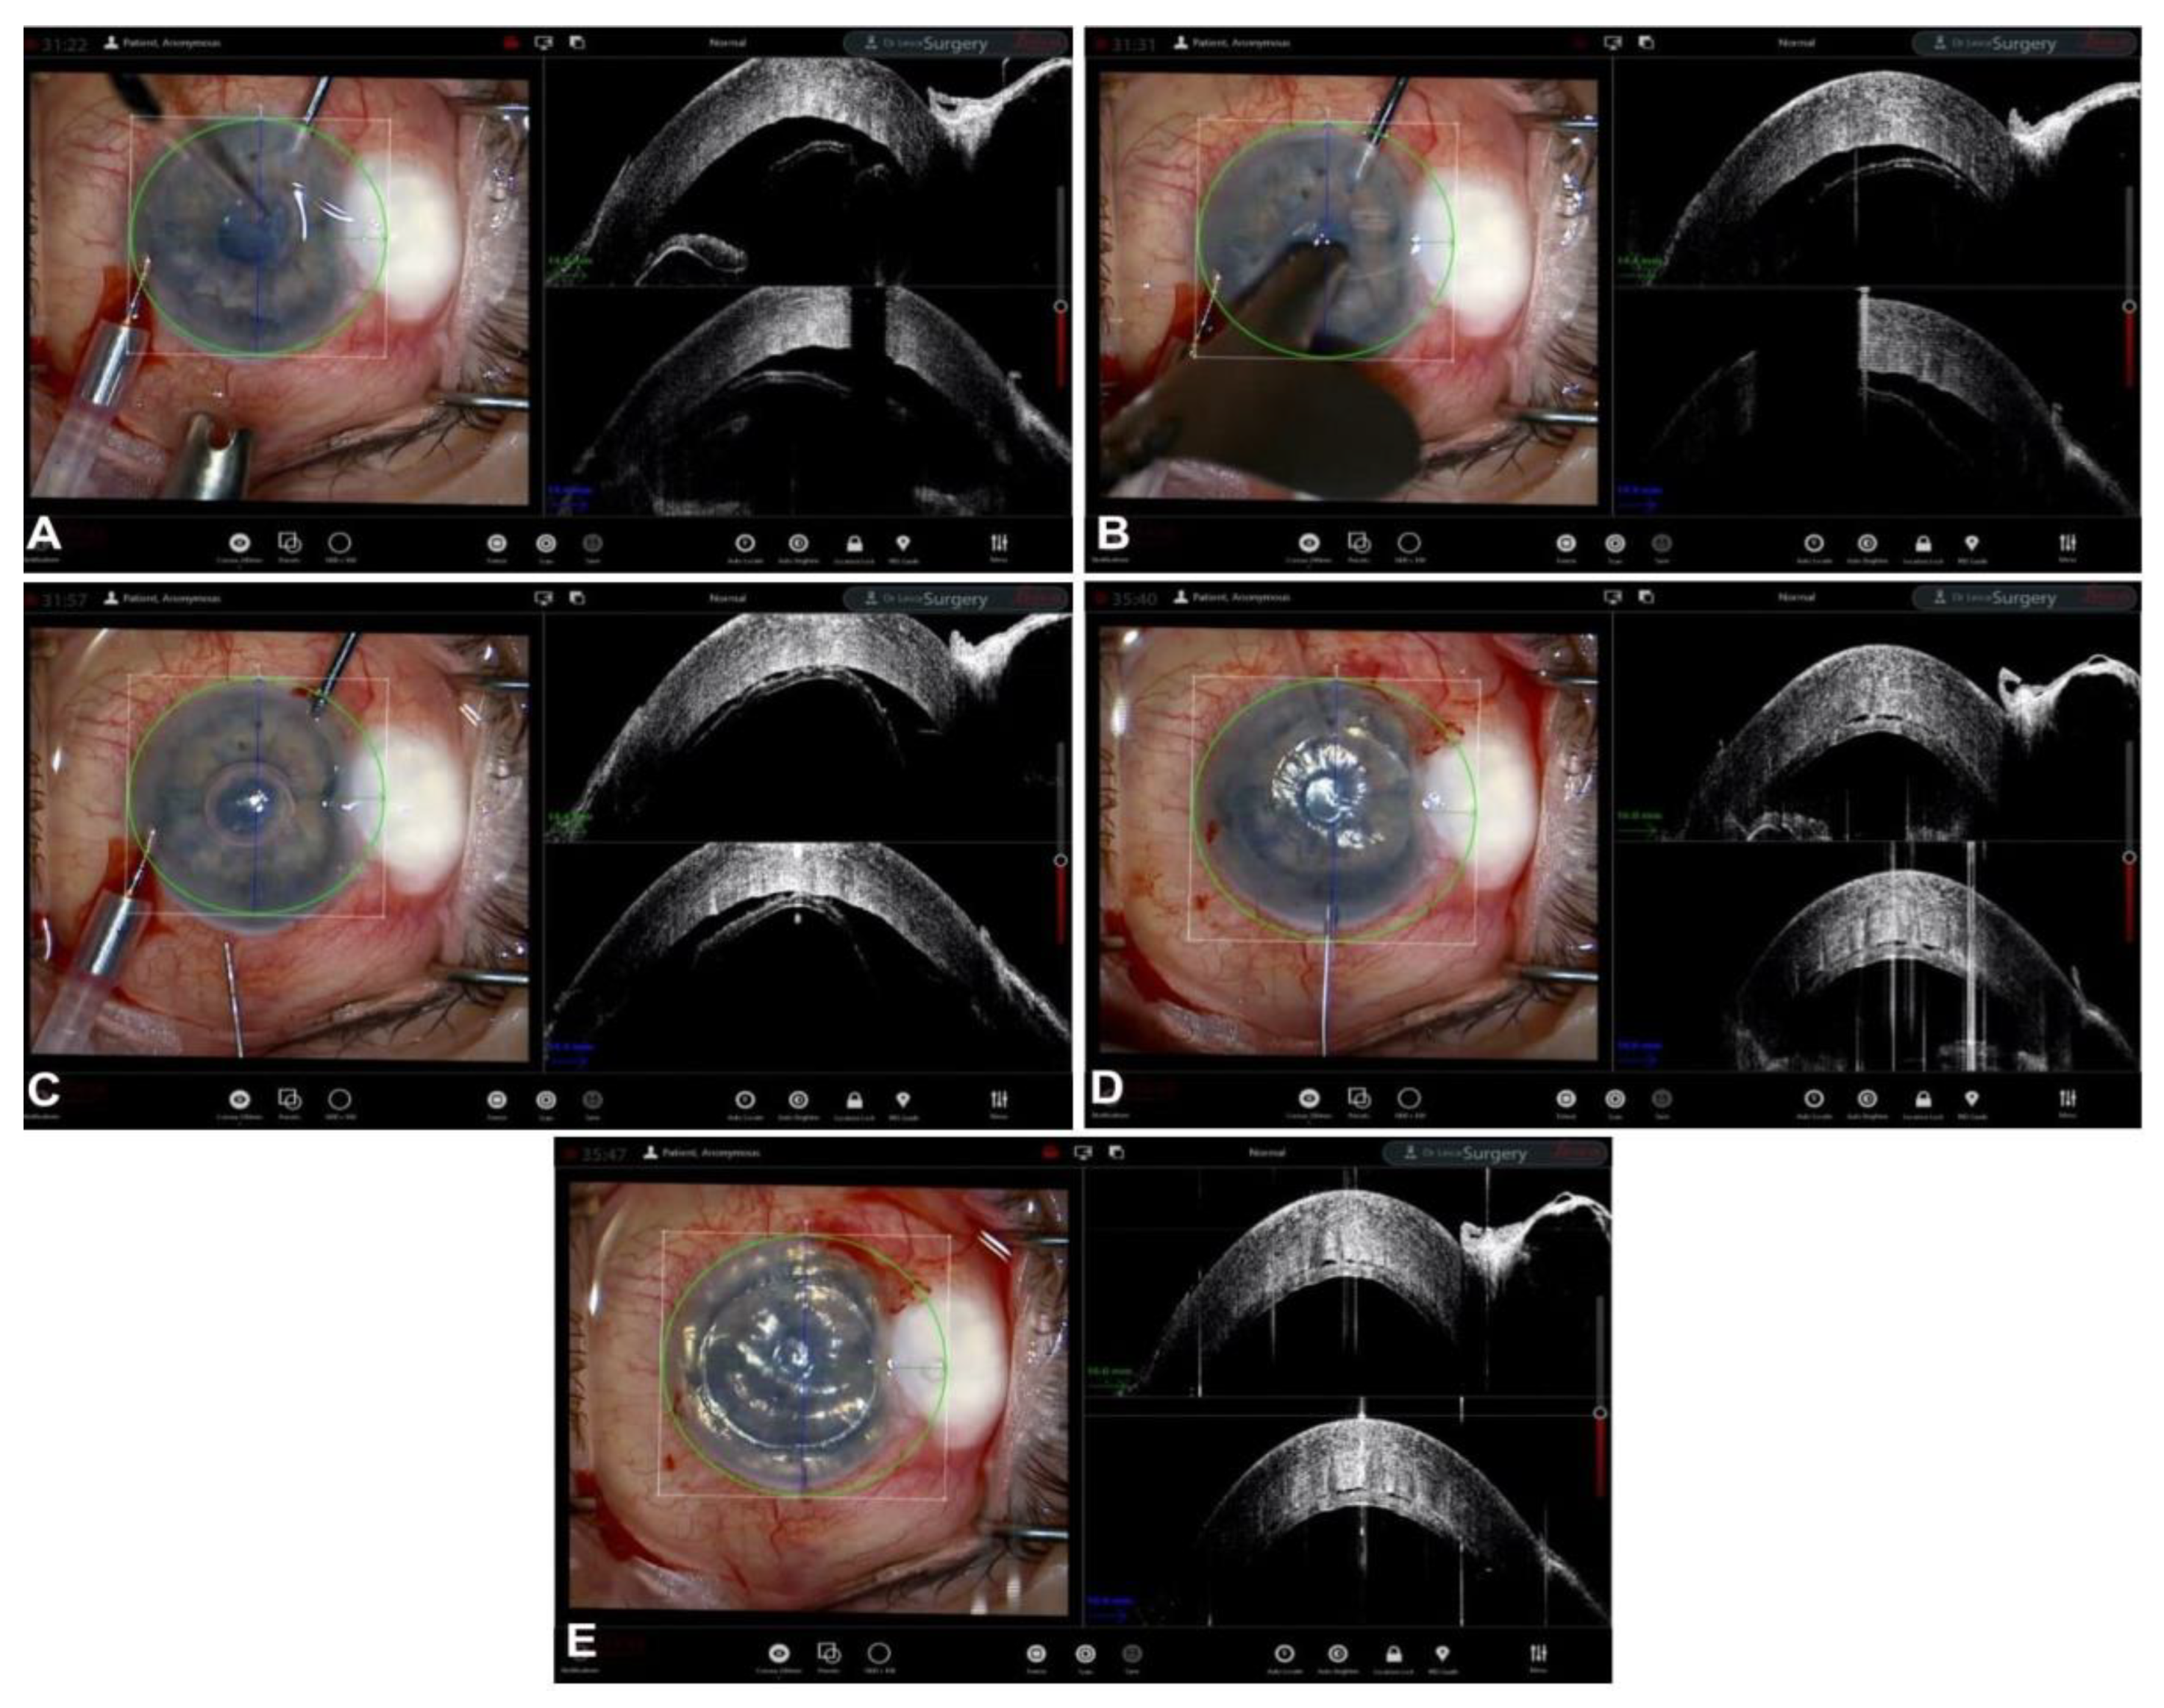

5. Guiding Descemet Membrane Endothelial Keratoplasty

- Steven, P.; Le Blanc, C.; Velten, K.; Lankenau, E.; Krug, M.; Oelckers, S.; Heindl, L.M.; Gehlsen, U.; Hüttmann, G.; Cursiefen, C. Optimizing Descemet Membrane Endothelial Keratoplasty Using Intraoperative Optical Coherence Tomography. JAMA Ophthalmol. 2013, 131, 1135–1142. [Google Scholar] [CrossRef] [PubMed]

- Sharma, N.; Sahay, P.; Maharana, P.K.; Kumar, P.; Ahsan, S.; Titiyal, J.S. Microscope Integrated Intraoperative Optical Coherence Tomography-Guided DMEK in Corneas with Poor Visualization. Clin. Ophthalmol. 2020, 14, 643–651. [Google Scholar] [CrossRef] [PubMed]

- Patel, A.S.; Goshe, J.M.; Srivastava, S.K.; Ehlers, J.P. Intraoperative Optical Coherence Tomography–Assisted Descemet Membrane Endothelial Keratoplasty in the DISCOVER Study: First 100 Cases. Am. J. Ophthalmol. 2019, 210, 167–173. [Google Scholar] [CrossRef]

- Muijzer, M.B.; Soeters, N.; Godefrooij, D.A.; van Luijk, C.M.; Wisse, R.P.L. Intraoperative Optical Coherence Tomography–Assisted Descemet Membrane Endothelial Keratoplasty: Toward More Efficient, Safer Surgery. Cornea 2020, 39, 674–679. [Google Scholar] [CrossRef] [PubMed]

- Cost, B.; Goshe, J.M.; Srivastava, S.; Ehlers, J.P. Intraoperative Optical Coherence Tomography–Assisted Descemet Membrane Endothelial Keratoplasty in the DISCOVER Study. Am. J. Ophthalmol. 2015, 160, 430–437. [Google Scholar] [CrossRef] [PubMed]

- Muijzer, M.B.; Heslinga, F.G.; Couwenberg, F.; Noordmans, H.-J.; Oahalou, A.; Pluim, J.P.W.; Veta, M.; Wisse, R.P.L. Automatic evaluation of graft orientation during Descemet membrane endothelial keratoplasty using intraoperative OCT. Biomed. Opt. Express 2022, 13, 2683. [Google Scholar] [CrossRef] [PubMed]

- Saad, A.; Guilbert, E.; Grise-Dulac, A.; Sabatier, P.; Gatinel, D. Intraoperative OCT-Assisted DMEK: 14 Consecutive Cases. Cornea 2015, 34, 802–807. [Google Scholar] [CrossRef] [PubMed]